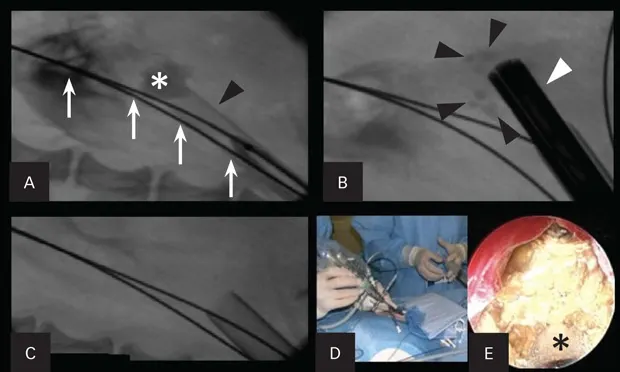

Figure 1. Percutaneous nephrolithotomy in a 3.1-kg female Yorkshire terrier with large nephroliths. Use of a percutaneous access kit under fluoroscopic guidance allows visualization of the large nephrolith (asterisk; A). The access sheath (black arrowhead) is inserted through the renal parenchyma over a dilation balloon. Two safety wires (white arrows) are present. The nephroscope (white arrowhead) is inserted through the sheath onto the stone with a lithotrite, breaking the large stone into fragments (black arrowheads; B). Fluoroscopic image after all stone fragments had been removed from the renal pelvis (C). The nephroscope being placed through the access sheath during percutaneous renal access (D). An endoscopic image of the nephrolith taken during lithotripsy (E). The lithotrite (asterisk) is seen through the working channel of the nephroscope.